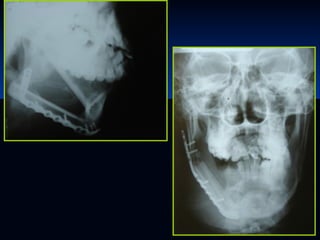

ESTUDIOS RADIOLOGICOS

SIALOGRAFIA

TAC

ECOGRAFIA

Radiografía simple:

Es útil para el estudio de las litiasis

radioopacas. Permite también excluir la

patología ósea mandibular que asemeja la

enfermedad glandular.